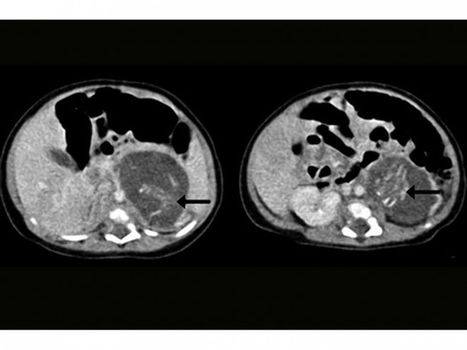

A Chinese baby has been born with two foetuses inside her body, in the latest case of an extremely rare phenomenon called foetus-in-fetu.

Doctors in Hong Kong successfully operated on the three-week-old girl, who was 9lb and otherwise healthy, removing the growths from her abdomen.

Originally believed to be tumours, doctors discovered the foetuses had developed to about 10 weeks and had a spine, some skin and the beginning of limbs, according to the Hong Kong Medical Journal.